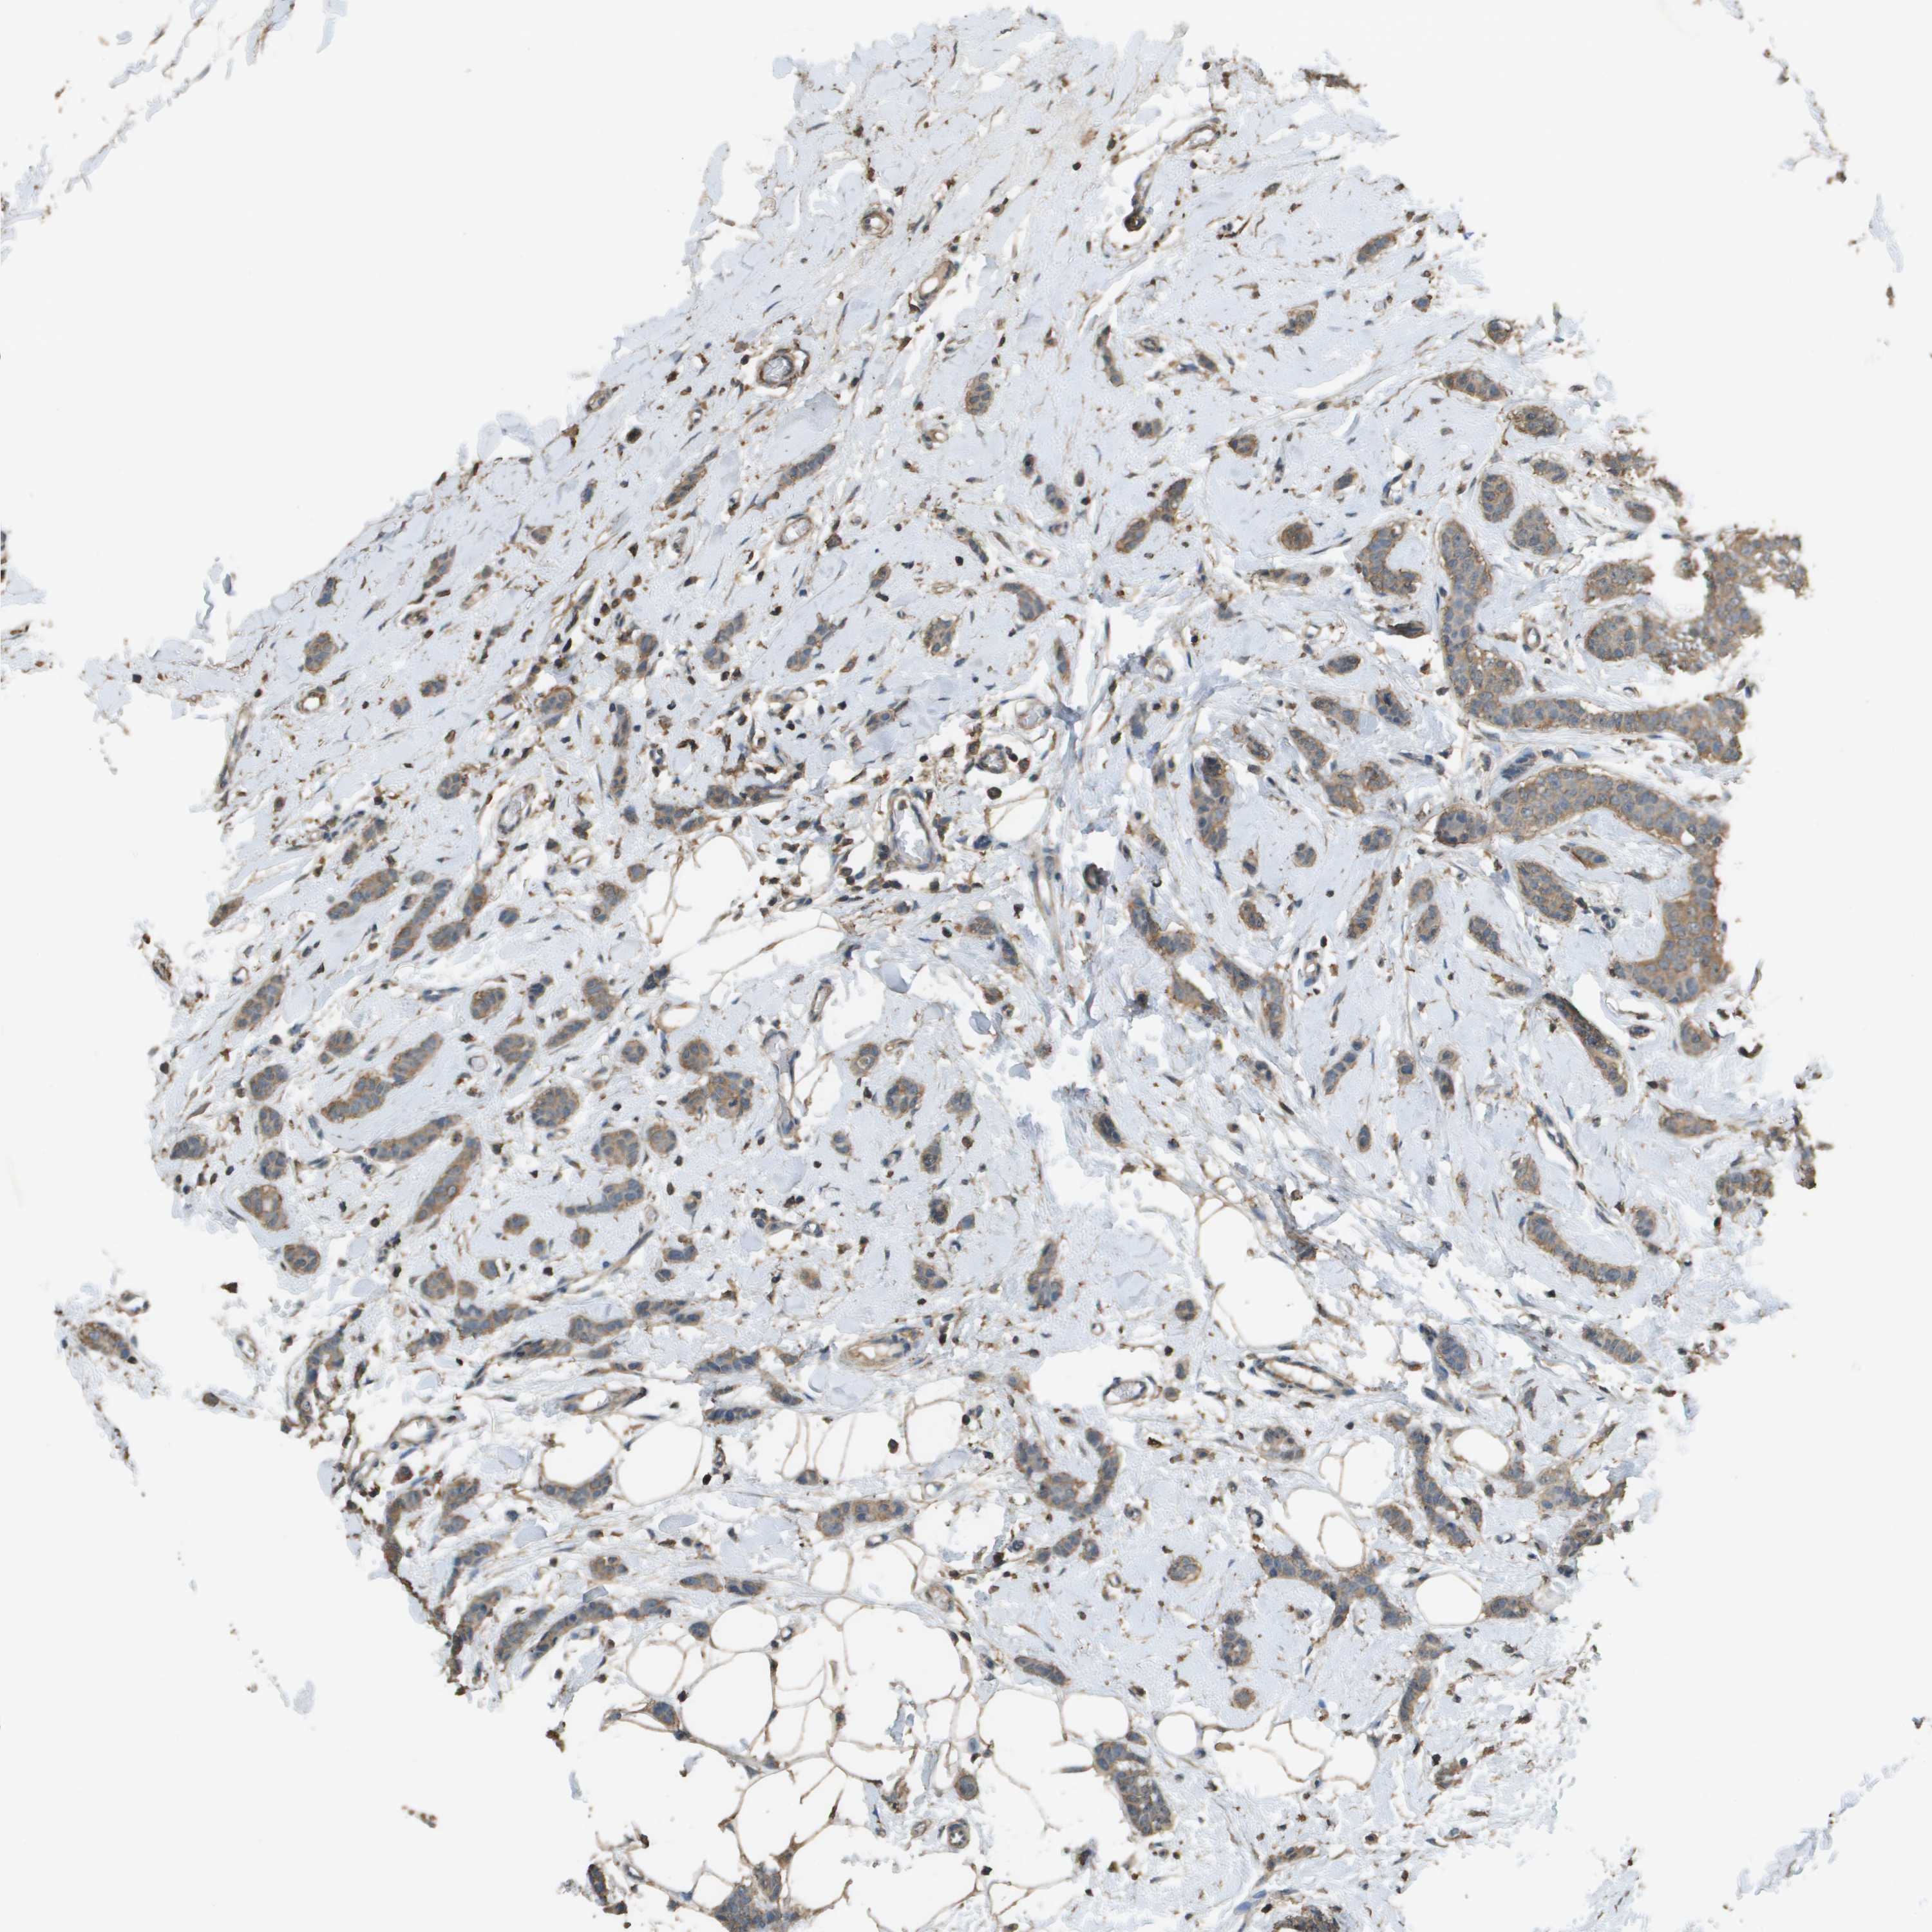

CANCER BREAST CANCER Show tissue menu

BRCA TCGA BRCA VALIDATION PROTEIN EXPRESSION

Breast cancer

Human cancer